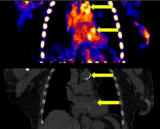

澳大利亚ANSTO获MRFF拨款 开发新型脑癌精准放射疗法

澳大利亚核科学与技术组织(ANSTO)作为牵头机构,首次获得医学研究未来基金(MRFF)拨款,将在四年内获得1,623,306美元,用于开发针对侵袭性脑癌的新型精准放射疗法——中子俘获增强粒子疗法(NCEPT)。该项目由Mitra Safavi-Naeini博士领导,是澳大利亚脑癌使命的一部分,旨在提高脑癌患者的生存率和生活质量。ANSTO已投入超过1.2亿美元,致力于改善脑癌治疗效果,此次获得的MRFF拨款,将进一步推动其在脑癌研究领域的进展。萨法维-纳伊尼博士表示:这项... 2025-12-09 放射医学